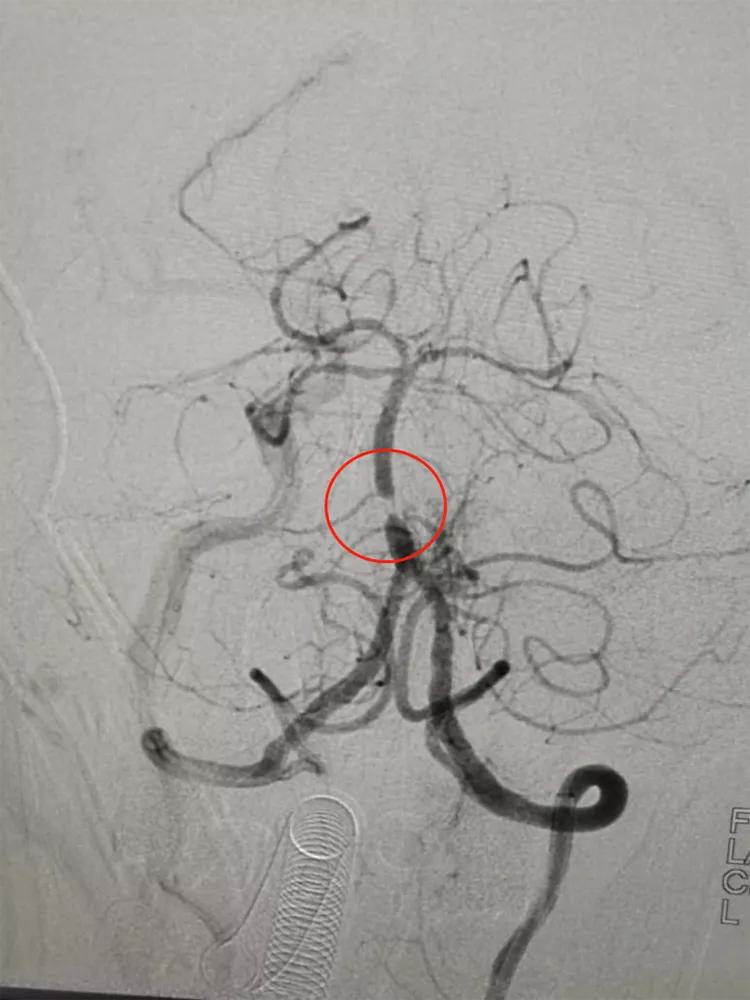

患者女性,53岁,因言语不能,右侧肢体乏力21小时入院。既往有高血压病史。入院查体:混合性失语,右上肢肌力2级,右下肢肌力3级。NIHSS评分9分。入院后经头颅CT、MRI等检查评估,诊断为急性脑梗死。在局部麻醉下做脑血管造影术,发现左侧大脑中动脉M1段闭塞。立即实施左侧大脑中动脉闭塞再通及支架成形术。术后第二天,患者言语功能完全恢复,右侧肢体肌力恢复正常,NIHSS评分0分。

支架成形术前,左侧大脑中动脉闭塞

支架成形术后,左侧大脑中动脉血流复通